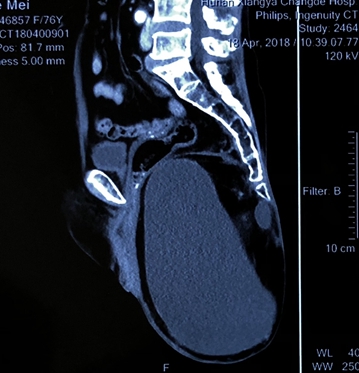

李老太来到湘雅常德医院整形美容烧伤科诊室时,坐都懒得坐,“坐着疼!”李老太不好意思地解释到,“我这是从小就有的毛病,现在大便也困难,睡觉也成问题,我已经好久都不能平躺了。怕是治不好了吧?”老太太再转过身,黄晓元教授便注意到了她臀部那颗“小皮球”,这就是导致老人家无法“落座”的原因。考虑为坐骨结节囊肿,大小约25cm*10cm。

最后,黄晓元教授与其团队——马铮铮、李连楚、金辉、唐宁宁、张文等人员在4 个小时的紧密配合中,克服了患者年龄大、手术范围广,肿块与直肠粘连紧密等问题,为李老太完美摘除了这个困扰了它七十多年的肿物。切除肿物经病理确诊为:尾肠囊肿来源的粘液性肿瘤。

据黄晓元教授介绍,尾肠囊肿是一种罕见的先天性囊肿,患者以女性居多,男女比例为3:1,确切的病因不清楚,最常见的是直肠局部的压迫症状,可有排便困难、排便疼痛等。目前主要治疗手段为手术完整切除。